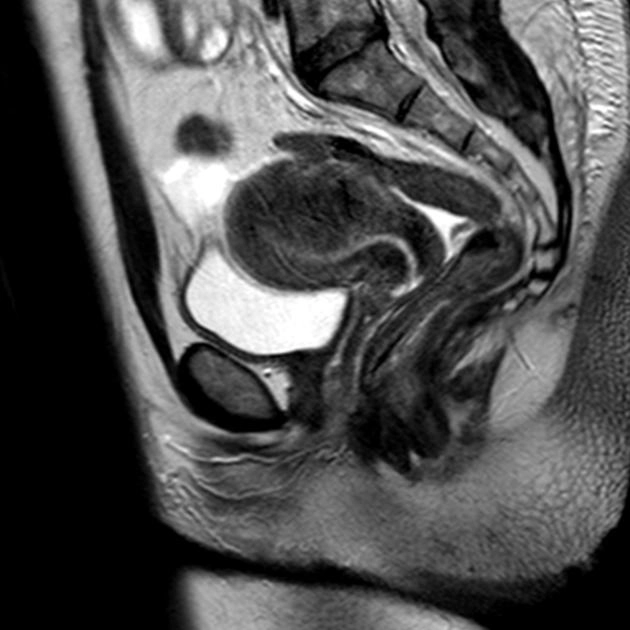

Bệnh cơ tuyến tử cung dạng nang (Cystic adenomyosis)